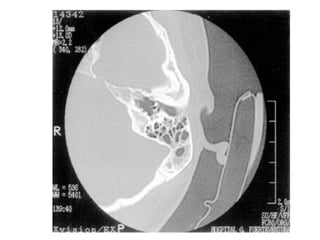

• Estudio radiológico:

Schüller, Stevens, Owens

TAC:

Valorar destrucción ósea.

Mastoiditis TC (erosión y ocupación

mastoideas).